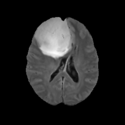

Pediatric MS Study

- Collaborator: Tanuja Chitnis PI (Brigham and Women's Hospital/Multiple Sclerosis Center), Alexander Zaitsev (Brigham and Women's Hospital/Surgical Planning Laboratory) and Massachusetts General Hospital

- Short description: Evaluate brain atrophy for pediatric MS Patients

- Image specification: 3 Tesla, Scanner: SIGNA HDx / GE MEDICAL SYSTEMS, 3D MPRAGE, Sagital Scans, TR/TI/TE=24/0/7 ms, pixel_xsize = 0.976600, pixel_ysize = 0.976600, fov = 250.009598, aspect = 1.535941, thick = 1.500000, space = 0.000000

- Used Task: MRI Human Brain